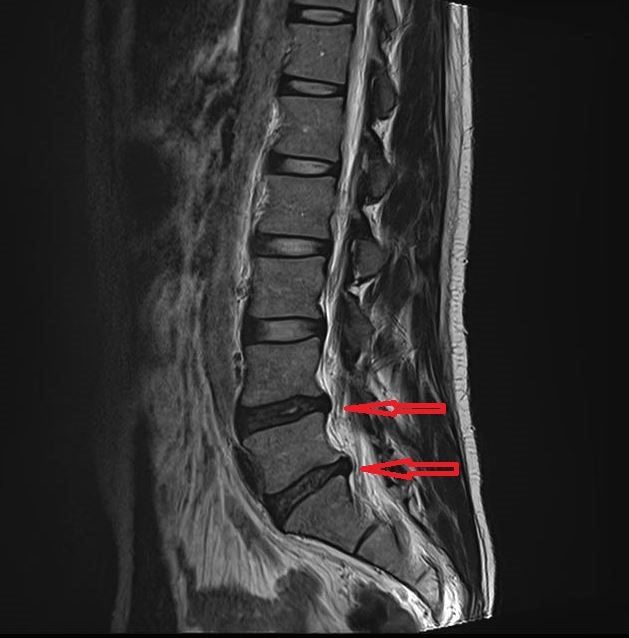

‘요추 추간판 탈출증’은 허리 통증과 함께 다리로 이어지는 저림이나 방사되는 통증을 동반하는 대표적인 척추 질환 중 하나입니다. 증상이 진행되면 단순한 통증뿐 아니라 다리의 근력에도 영향을 줄 수 있습니다. 예를 들어 까치발로 서거나 뒤꿈치로 서는 동작이 어려워지는 경우도 나타날 수 있습니다.

1단계 : 디스크의 퇴행 변화가 시작되는 단계

2단계 : 디스크가 밖으로 돌출된 단계

3단계 : 디스크 내부 수핵이 밖으로 탈출한 단계

4단계 : 탈출된 수핵이 아래쪽으로 이동하는 단계

환자마다 증상의 강도와 회복 과정이 다르기 때문에 단계에 따라 접근 방법도 달라질 수 있습니다.

일반적으로 1~2단계에서는 통증과 저림이 비교적 완만하고 관리에 대한 반응이 빠른 편입니다. 반면 3~4단계에서는 통증 강도가 높아 일상생활이 어려워질 수 있으며 입원 관리가 필요하기도 합니다. 급성 통증이 발생한 뒤 약 2~3주 정도의 급성기를 지나면 이후 외래 진료를 통해 남아있는 증상을 줄여가는 과정이 진행될 수 있습니다.

디스크 : 돌출되거나 탈출한 수핵이 신경을 압박하여 증상이 발생